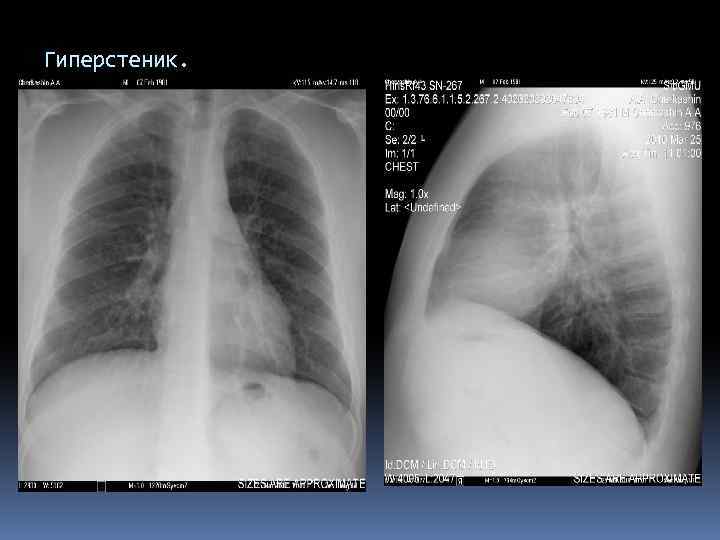

Гиперстеник.

Гиперстеник. Конфигурация ССС.